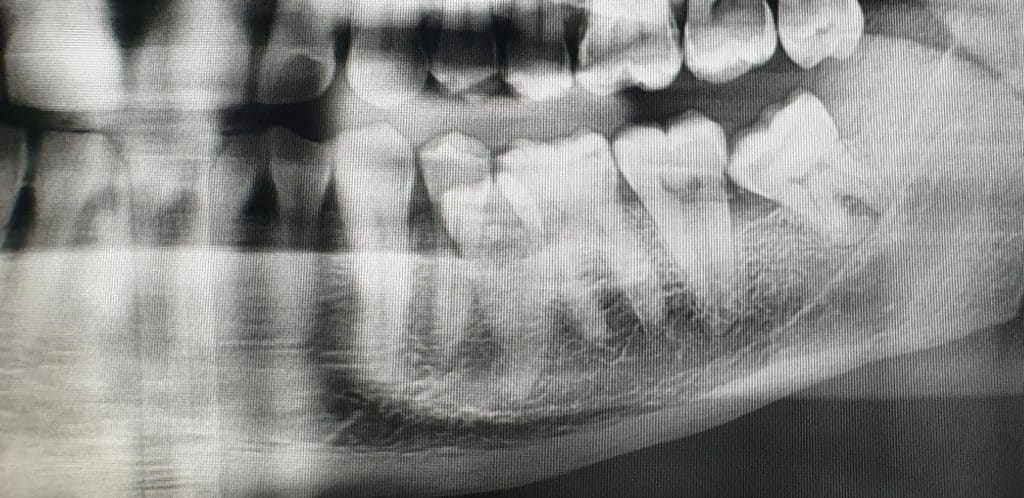

All’esame clinico si evince la posizione anomala del 3.5 e dopo aver effettuato OPT, si opta per l’avulsione dell’elemento dentario interessato.

L’avulsione ha presentato un discreto livello di difficoltà vista la posizione e lo stretto rapporto col 3.4, tanto da ipotizzare l’avulsione anche del 3.4.

L’estrazione è stata portata a termine con successo, il dente ha presentato radice curva e nella zona interessata dell’estrazione si è provveduto a inserire spugnetta emostatica ed osso sintetico e sutura.